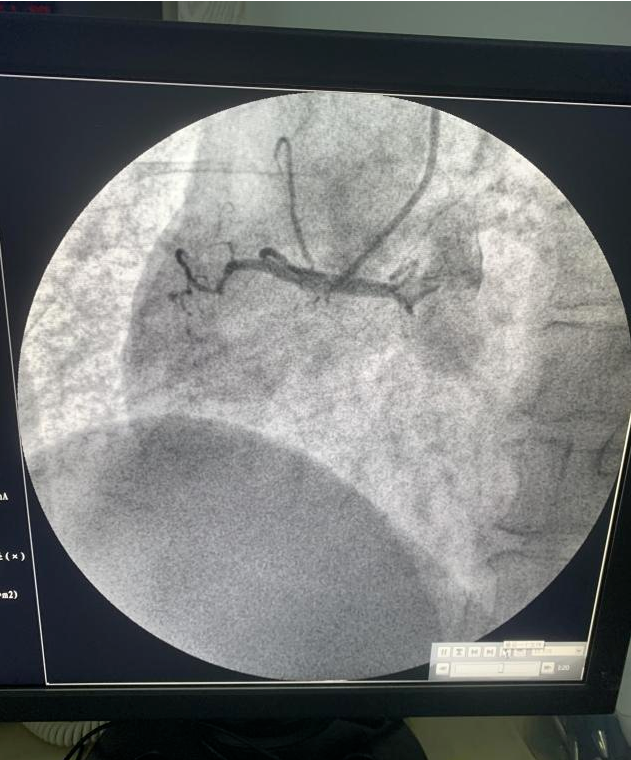

施教授到院后,立即查房评估患者情况,做术前交待病情。得到患者家属同意并签字后,立刻前往导管室。此时,冠脉造影检查显示右冠脉闭塞。

施教授评估血管情况后,凭借着多年丰富的临床经验很快使导丝通过闭塞血管,立即选择合适的预扩球囊开张。